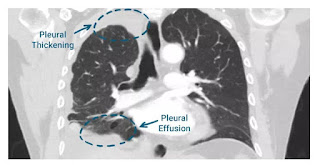

When a person goes to the doctor with early signs of malignant pleural mesothelioma a ct scan of the chest is often the next step in making a diagnosis. Eighteen years experience in turkey. Appearances are typical of pleural mesothelioma especially given the evidence of underlying asbestos related pleural disease.

The importance of imaging. The 3 d images ct scans provide a far more detailed view and offer more than 90 percent detection sensitivity. Differentials to consider would be pleural metastasis or invasive thymoma with pleural spread although these would be much less likely in this particular case.

Development of a guideline on reading ct images of malignant pleural mesothelioma and selection of the reference ct films european journal of radiology vol. Pleural mesothelioma 90 covered in this article. Ct scans enable doctors to identify the stage of a tumor by exposing whether the tumor has spread to nearby tissues lymph nodes or to distant organs.

12 clinical characteristics treatment and survival outcomes in malignant mesothelioma. Imaging is important in diagnosing mesotheliomait will provide information such as the extent of disease in the original organ and also show if the cancer has spread to. A ct scan otherwise known as a computerized or computed tomography scan requires the patient to lie on a small bench which is moved through a doughnut shaped imaging device.